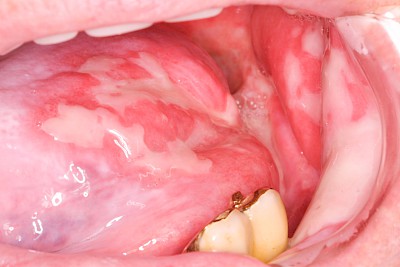

Kauen auf Wange, Zunge & Lippen

Das Kauen auf Wange, Zunge oder Lippen zählt zu den sogenannten Habits und ist meist stressbedingt. Diskrete Linien (Verhornungsleisten) oder aber unruhige Schleimhautareale bis hin zu Erscheinungsformen wie "wildes Fleisch" können dabei auffallen.

Beispiele32 Bilder